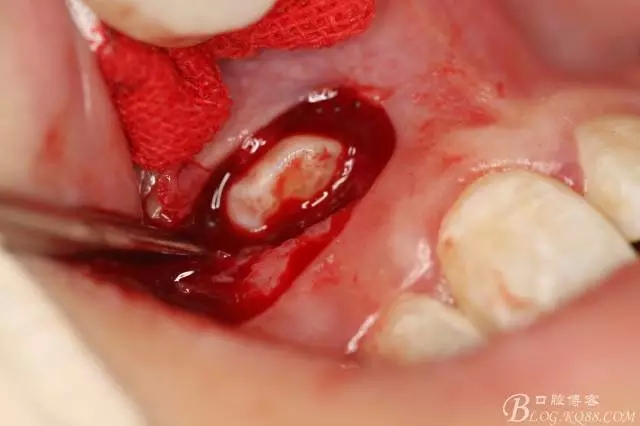

病例資料: 患者、柴xx、女、16歲。專科檢查及病歷如下圖: 患者同意我院正畸科建議,遂轉(zhuǎn)診倒外科。術(shù)前簽知情同意書。 治療過程: 圖1.術(shù)前的CBCT檢查:13阻生,疑為含牙囊腫。縱剖面顯示12牙根吸收至根尖1/3。 圖2.局部麻醉下 。行唇側(cè)弧形切口,12松動不到1°。 圖3.翻瓣、暴露骨面。 圖4.去骨、 暴露13牙冠 圖5.去骨、逐漸顯露13。 圖7.拔除13. 圖8.摘除囊壁 圖9.必須完整剝離囊壁。 圖10.摘除囊壁后形成的骨腔 圖11.超聲骨刀12根尖倒預(yù)備 圖13. 消毒棉球骨腔內(nèi)隔濕血液,紙尖干燥倒預(yù)備好的根管 圖14. 紙尖無血即可 圖15。MTA倒充填 圖16.骨腔填塞膠原蛋白海綿 圖17.拔除的13及摘除的囊壁 圖18.縫合 圖19.術(shù)后x線根尖片影像:MTA封閉根尖